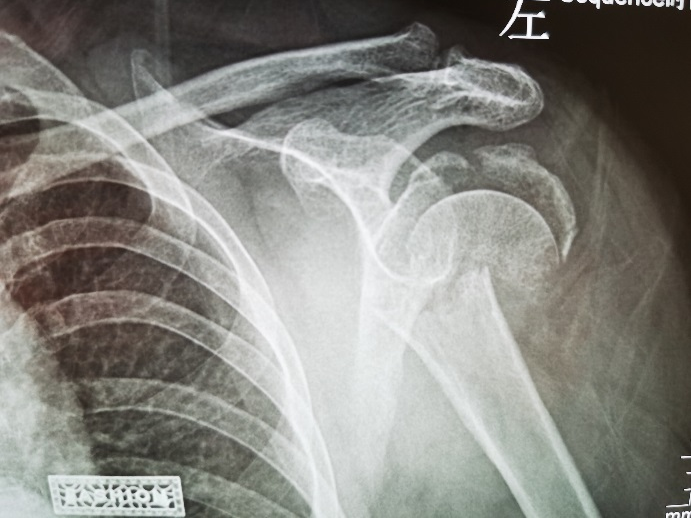

接受手术的患者是一位年过七旬的胡奶奶,因不慎跌倒致左肩部剧烈疼痛、肿胀难忍,活动完全受限。入院后,骨一科团队为其进行了详细的影像学检查,结果显示患者为 “肱骨近端粉碎性骨折(Neer 分型 IV 型/四部分骨折)”,肱骨头碎裂成数块,且伴有骨质疏松。

术前X光片